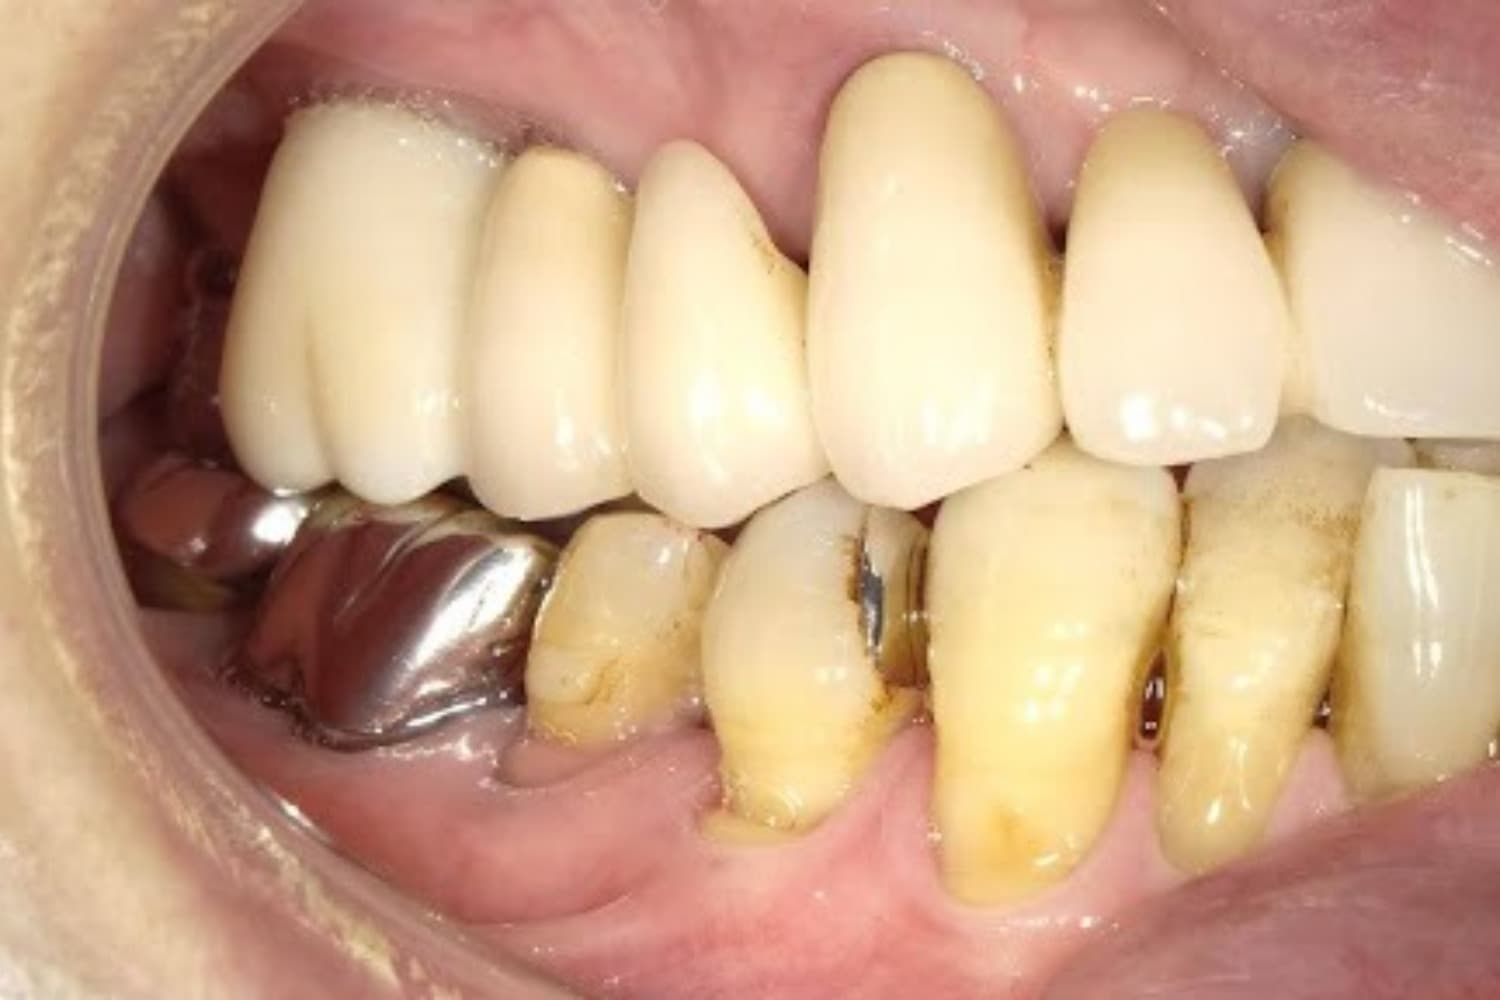

左上の歯のインプラント治療(40代女性)

Before

After

抜歯をおこない上顎洞内及び歯抜した周囲組織の回復を試みたあと、グラフトレスサイナスリフト・人口骨補填をともなうインプラント治療

50代

女性

主訴

左上の歯が歯根破折を起こしていた。何もしていなくとも痛みを感じる。

2ヵ月半

6回

368,500円(税込) 費用の内訳: 【インプラント基本料】330000円(税込み) 基本料金に以下を含む ・フィックスチャー及び手術費用 ・投薬費用、 ・レントゲン費用 ・インプラント上部費用(アバットメントおよびジルコニアクラウンの費用用) 【オプション費用】 ・グラフトレスサイナスリフト費用+人工骨費用 38500円(税込み)

・手術後に痛み・腫れ・出血・合併症等を引き起こす恐れがあります。 ・噛む感覚がご自身の歯と異なることがあります。 ・見た目がご自身の歯と異なる場合があります。 ・手術後もメインテナンスを続けないと、インプラントが抜け落ちてしまう恐れがあります。